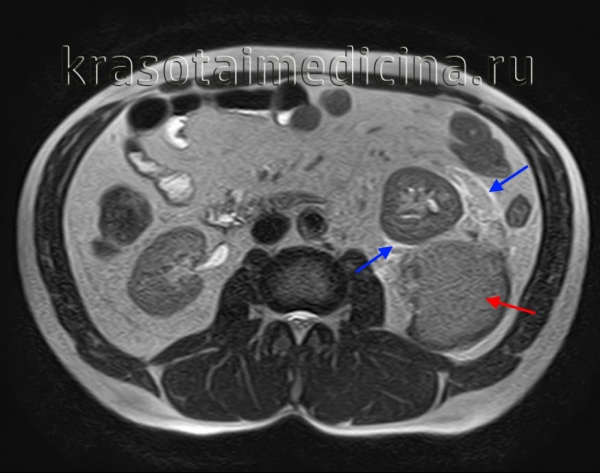

МРТ ОБП: повреждение левой почки, забрюшинная гематома (красная стрелка), отек перинефральной клетчатки (синяя стрелка).